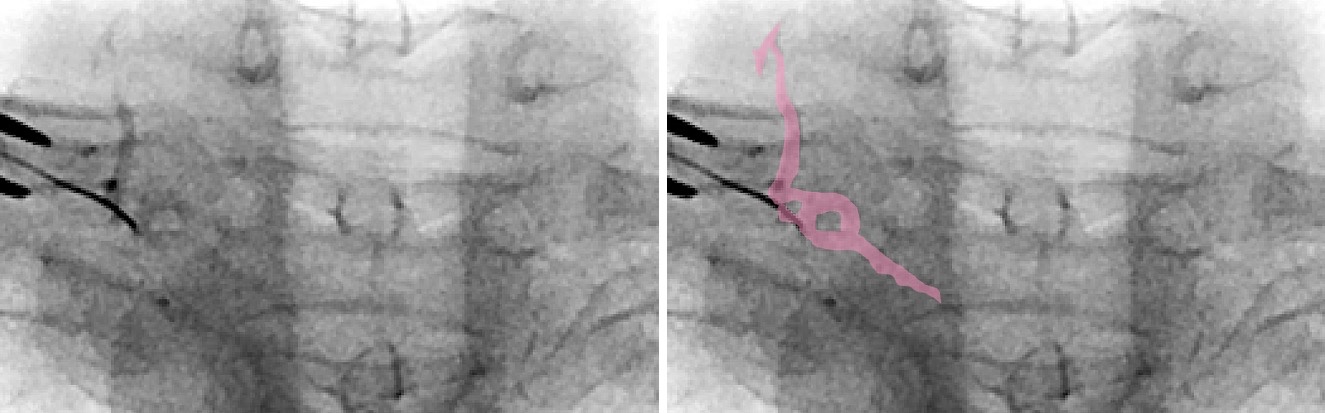

- Venous contrast spread, characterized by irregular diffusion and slow disappearance, may indicate contact with the external vertebral venous plexus. Advancing the needle, 2–3 mm often reaches the nerve root (Figure 6).

Pink area = contrasted veins